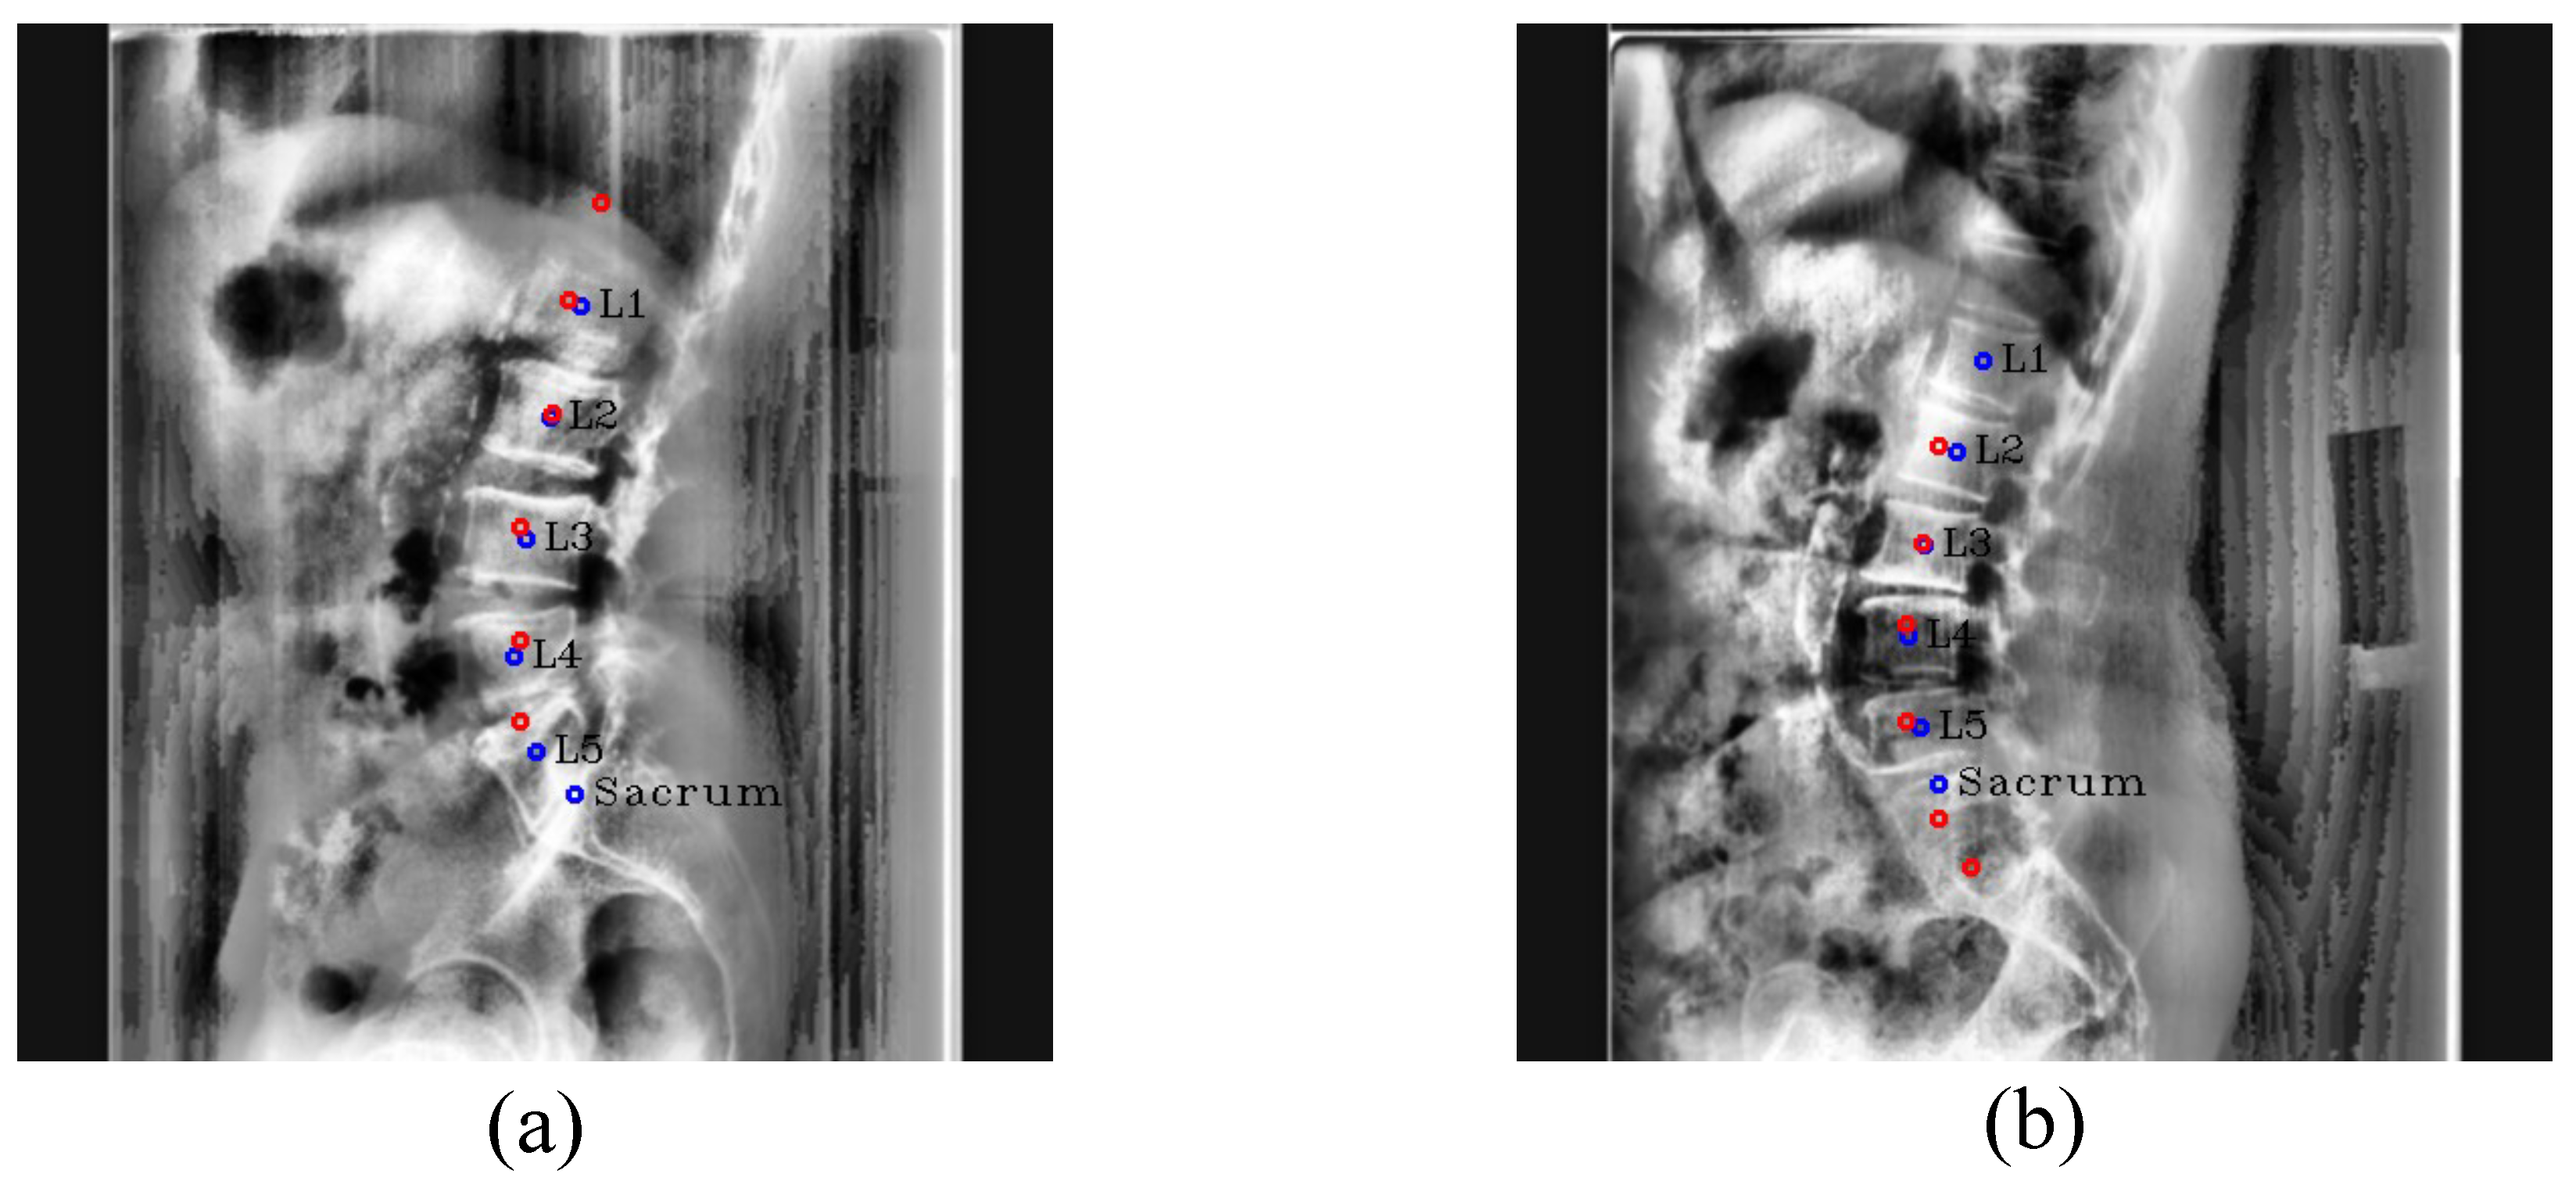

Figure 19. Results of center detection. Our results are (a,c), and the results of Kim et al. [5] are (b,d). The red circles denote the predicated centers of L1, L2, L3, L4, L5, and the sacrum in order from the top, and the blue circles and labels denote the ground truth of the center of each vertebra.

We compared the performances of our method and Kim et al. [5] as the previous method quantitatively and qualitatively. For a fair comparison, the network of Kim et al. was modified from a segmentation task to a landmark detection task, and we considered the results of lumbar vertebrae since there was no result for the sacrum in Kim et al.

Center detector:Table 10 shows that our overall center detection ability was superior to Kim et al., particularly in terms of the outlier ratio and the distance error of L1. When localizing the center of each lumbar vertebra, Kim et al. generated a center confidence map of 1 channel and extracted the center coordinates of the lumbar vertebrae. At this time, in the case of L1, the confidence score was low when obscured by thoracic structures, as shown in the Discussion Section of [5], making it challenging to extract local maximum coordinates through the post-processing of Kim et al. Moreover, Kim et al. eliminated the confidence map when the confidence score was too low, and there were many outlier cases in which the center coordinates were not extracted for L1 because of the elimination, as shown in Figure 19. In addition, the predicted location of the centers was slightly different from the ground truth. However, our method can detect more accurately using a wide convolution filter size and RSC. Furthermore, even when some of the target center coordinates were not extracted, we used the multi-channel confidence map including the confidence map with low confidence scores during the post-processing step to ensure that all center coordinates were extracted.

Landmark detector: As shown in Table 11, our method outperformed Kim et al. in every vertebral landmark detection, except L3. Especially, our network showed lower distance errors of 16.3259 pixels and 10.3488 pixels, respectively, for L1 and L2 compared to Kim et al. When landmarks were barely visible, such as L5 in the first row and L1–L2 in the second row of Figure 20, unlike Kim et al., which detected landmarks solely based on visuals, our method was much better as it predicted landmarks using location and morphological information through CoordConv and PAFs. Furthermore, Kim et al. often incorrectly predicted vertebral landmarks, even when the landmarks were a little occluded, as in the third row and fourth row. As a result, the standard deviation of the distance error values was very high, as shown in Table 11, indicating that it was not detected reliably. However, thanks to CoordConv and PAFs, our method achieved better landmark detection accuracy and reliability.